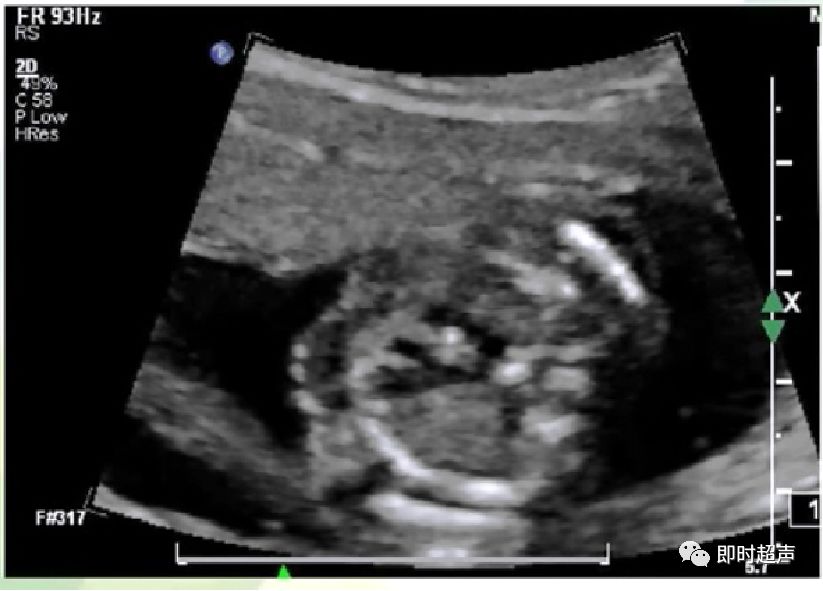

侧动探头连续观察即可观察到动脉导管走形迂曲,但还是汇入降主动脉

动脉导管瘤

胎儿动脉导管瘤的预后

- 动脉导管迂曲扩张和动脉导管瘤对新生儿最常见的影响就是动脉导管未闭。但随着研究的深入,发现动脉导管未闭的发生率并不是很高。

- 但有文献报道,少数动脉导管瘤会发生严重的并发症,甚至导致新生儿死亡。因此,如在产前发现动脉导管瘤或迂曲扩张,应提示临床并追踪。